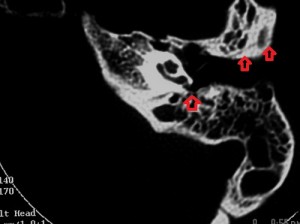

Images A and B are bone-window axial sections of the petrous portions of the right and left temporal bones taken at slightly different levels. Both show longitudinal fractures of the petrous pyramids with slightly different orientations (see the arrows). In addition, there is a fracture line through the anterior right basi-occiput, arrowed on image B.

On the right, the fracture line extends into the right middle ear, across the tegmen tympani and into the middle cranial fossa while on the left it stops at the external auditory meatus. The right ossicular chain is dislocated (incudostapedial joint) but the left chain and the right and left otic capsules are preserved. There is effluent in the right mesotympanum, the reason for a right ottorhea at presentation. There is no fluid in the left middle and external ear. Although the images are not included, there are no injuries to the internal auditory canals

1. Longitudinal fractures of the right and left petrous pyramids with right ossicular chain dislocation.